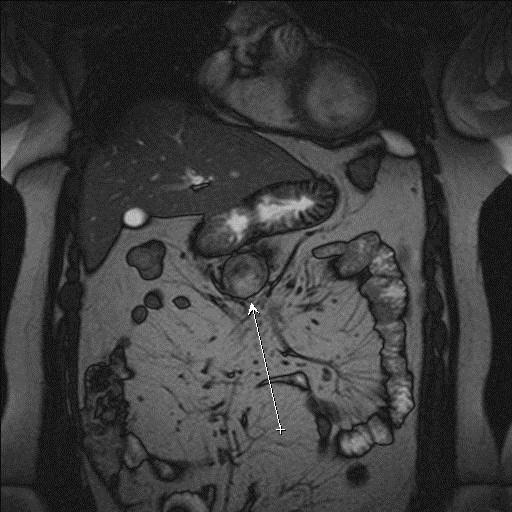

Незважаючи на значну кількість діагностичних методів, що існують для дослідження стану легень, серця, печінки, нирок, шлунка, кишечника, жовчного міхура та підшлункової залози, МРТ часто виявляється необхідним, а іноді - єдиним ефективним способом отримання цінної інформації про структуру та функції органів грудної та черевної порожнин. Наприклад, не існує жодного порівнянного по інформативності з МРТ методу дослідження стану розташованих за грудиною структур (вилочкової залози, лімфатичних вузлів, в деяких ситуаціях - серця і його судин). В інших випадках, коли є протипоказання до застосування традиційних діагностичних прийомів, МРТ також може виявитися єдиним ефективним діагностичним методом.